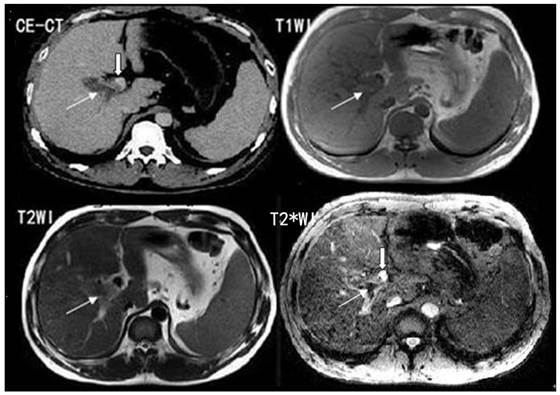

For portal vein visualization, there was no significant score difference in left, middle and right portal veins between CE-CT and T2*WI (t = -1.76- 1.35, p>0.05) (Figure 2; Table 2).

Fig 2

T2*WI showing good left, middle and right portal vein visualization. White arrows show the left, middle and right portal vein.

Int J Med Sci Image